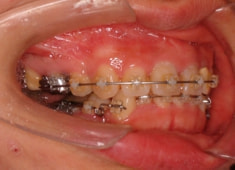

治療開始から1年8ヶ月後